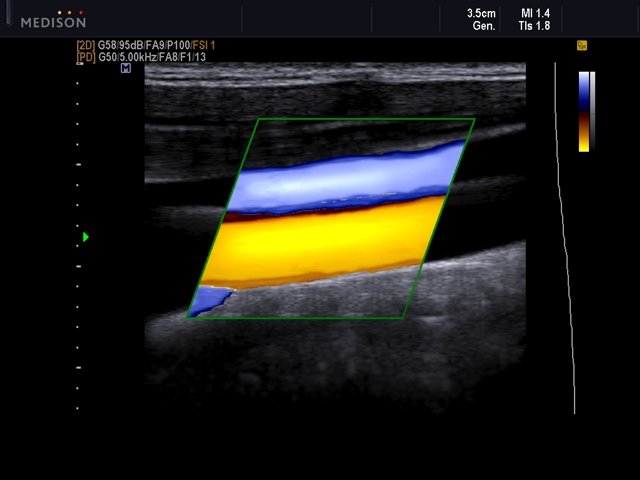

- DPD - направленный энергетический допплер.

TD-режим (тканевой допплер): количественная оценка локальной сократительной функции стенок ЛЖ и ПЖ. - Сонные артерии: автоматическая, полуавтоматическая, ручная трассировка доплеровского спектра; ПСС, КДС, %СтПлощ, %Ст Диам, площадь сосуда, диаметр сосуда, средняя толщина интимы, объемный кровоток.

- Артерии верхних конечностей: автоматическая, полуавтоматическая, ручная трассировка доплеровского спектра; ПСС, КДС, %СтПлощ, %Ст Диам, площадь сосуда, диаметр сосуда, объемный кровоток.

- Артерии нижних конечностей: автоматическая, полуавтоматическая, ручная трассировка доплеровского спектра; ПСС, КДС, %СтПлощ, %Ст Диам, площадь сосуда, диаметр сосуда, объемный кровоток.